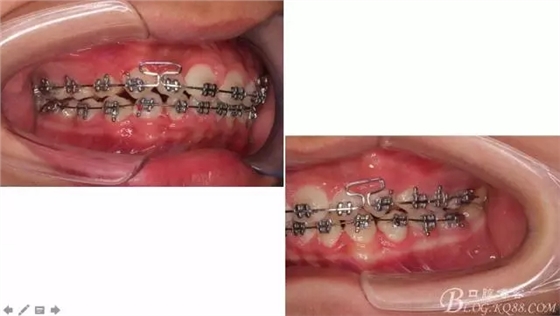

看看口內(nèi)照吧!真象“大暴牙”v假象“大暴牙”

三度深覆合,三度深覆蓋,尖牙,磨牙均二類關(guān)系!

佩戴三個月的FR2, 效果奇佳!前牙基本達(dá)到淺覆蓋,淺覆合!接下來進(jìn)入二期直絲弓固定正畸,排齊階段!

接下來盡管配合些雙側(cè)后牙對角牽引,咬合關(guān)系依,不盡人意。

下頜配合多曲方絲,三角牽引,調(diào)整咬合。